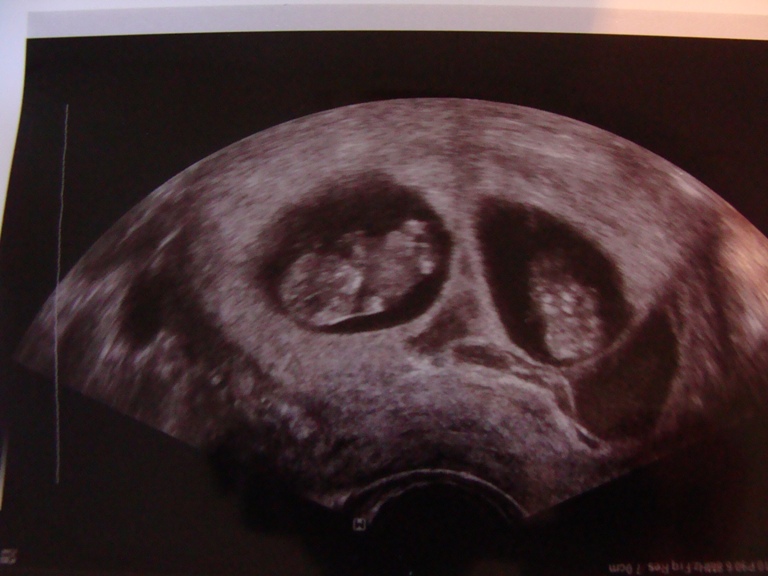

1 узи

2 узи 9 неделй

3 13 неделй